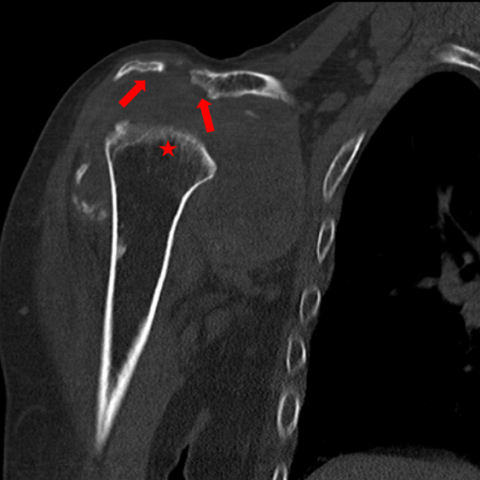

CT冠状面(a)和轴面(b)计算机断层扫描图像显示肱骨头和关节盂(*)有广泛破坏。肩峰下表面和锁骨外侧端也可见骨质溶骨性破坏(箭)。关节囊可见钙化(弯箭),关节内不规则钙沉积(箭头)存在。